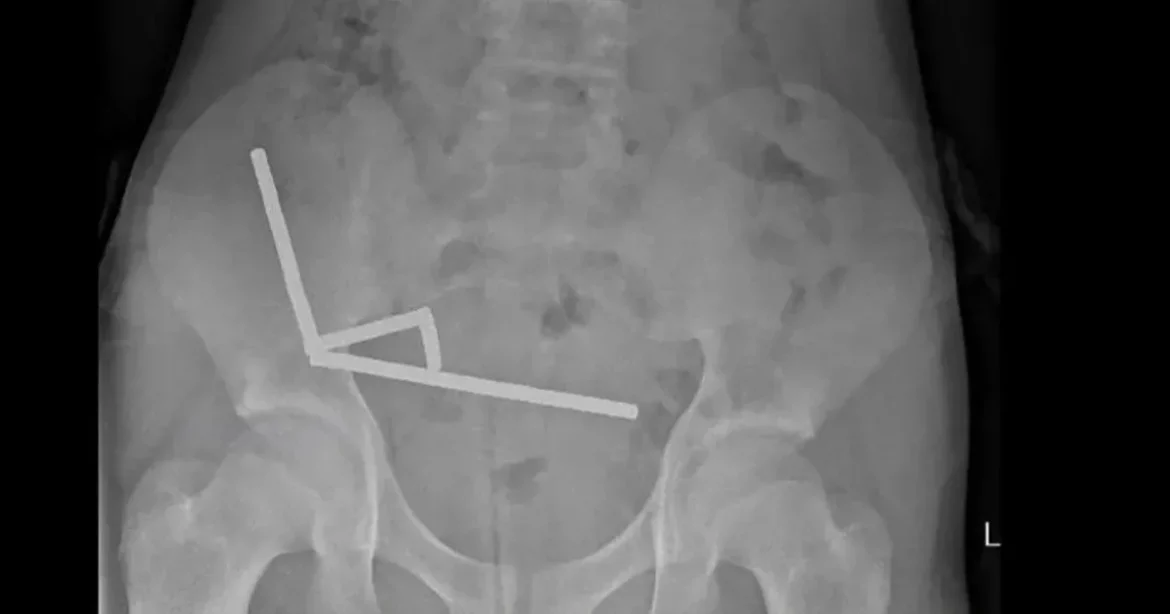

Miután a fiú lenyelte a mágnest, amelyek egymáshoz tapadtak a beleiben, hasi görcsök kezdődtek. Négy nap szenvedés után került a Tauranga Kórházba, ahol a sebészeknek sürgősen kellett beavatkozniuk. A mágnesek nyomása négy ponton a szövetek elhalását okozta, ami súlyosbította a helyzetet, és lehetetlenné tette a normális bélműködést.